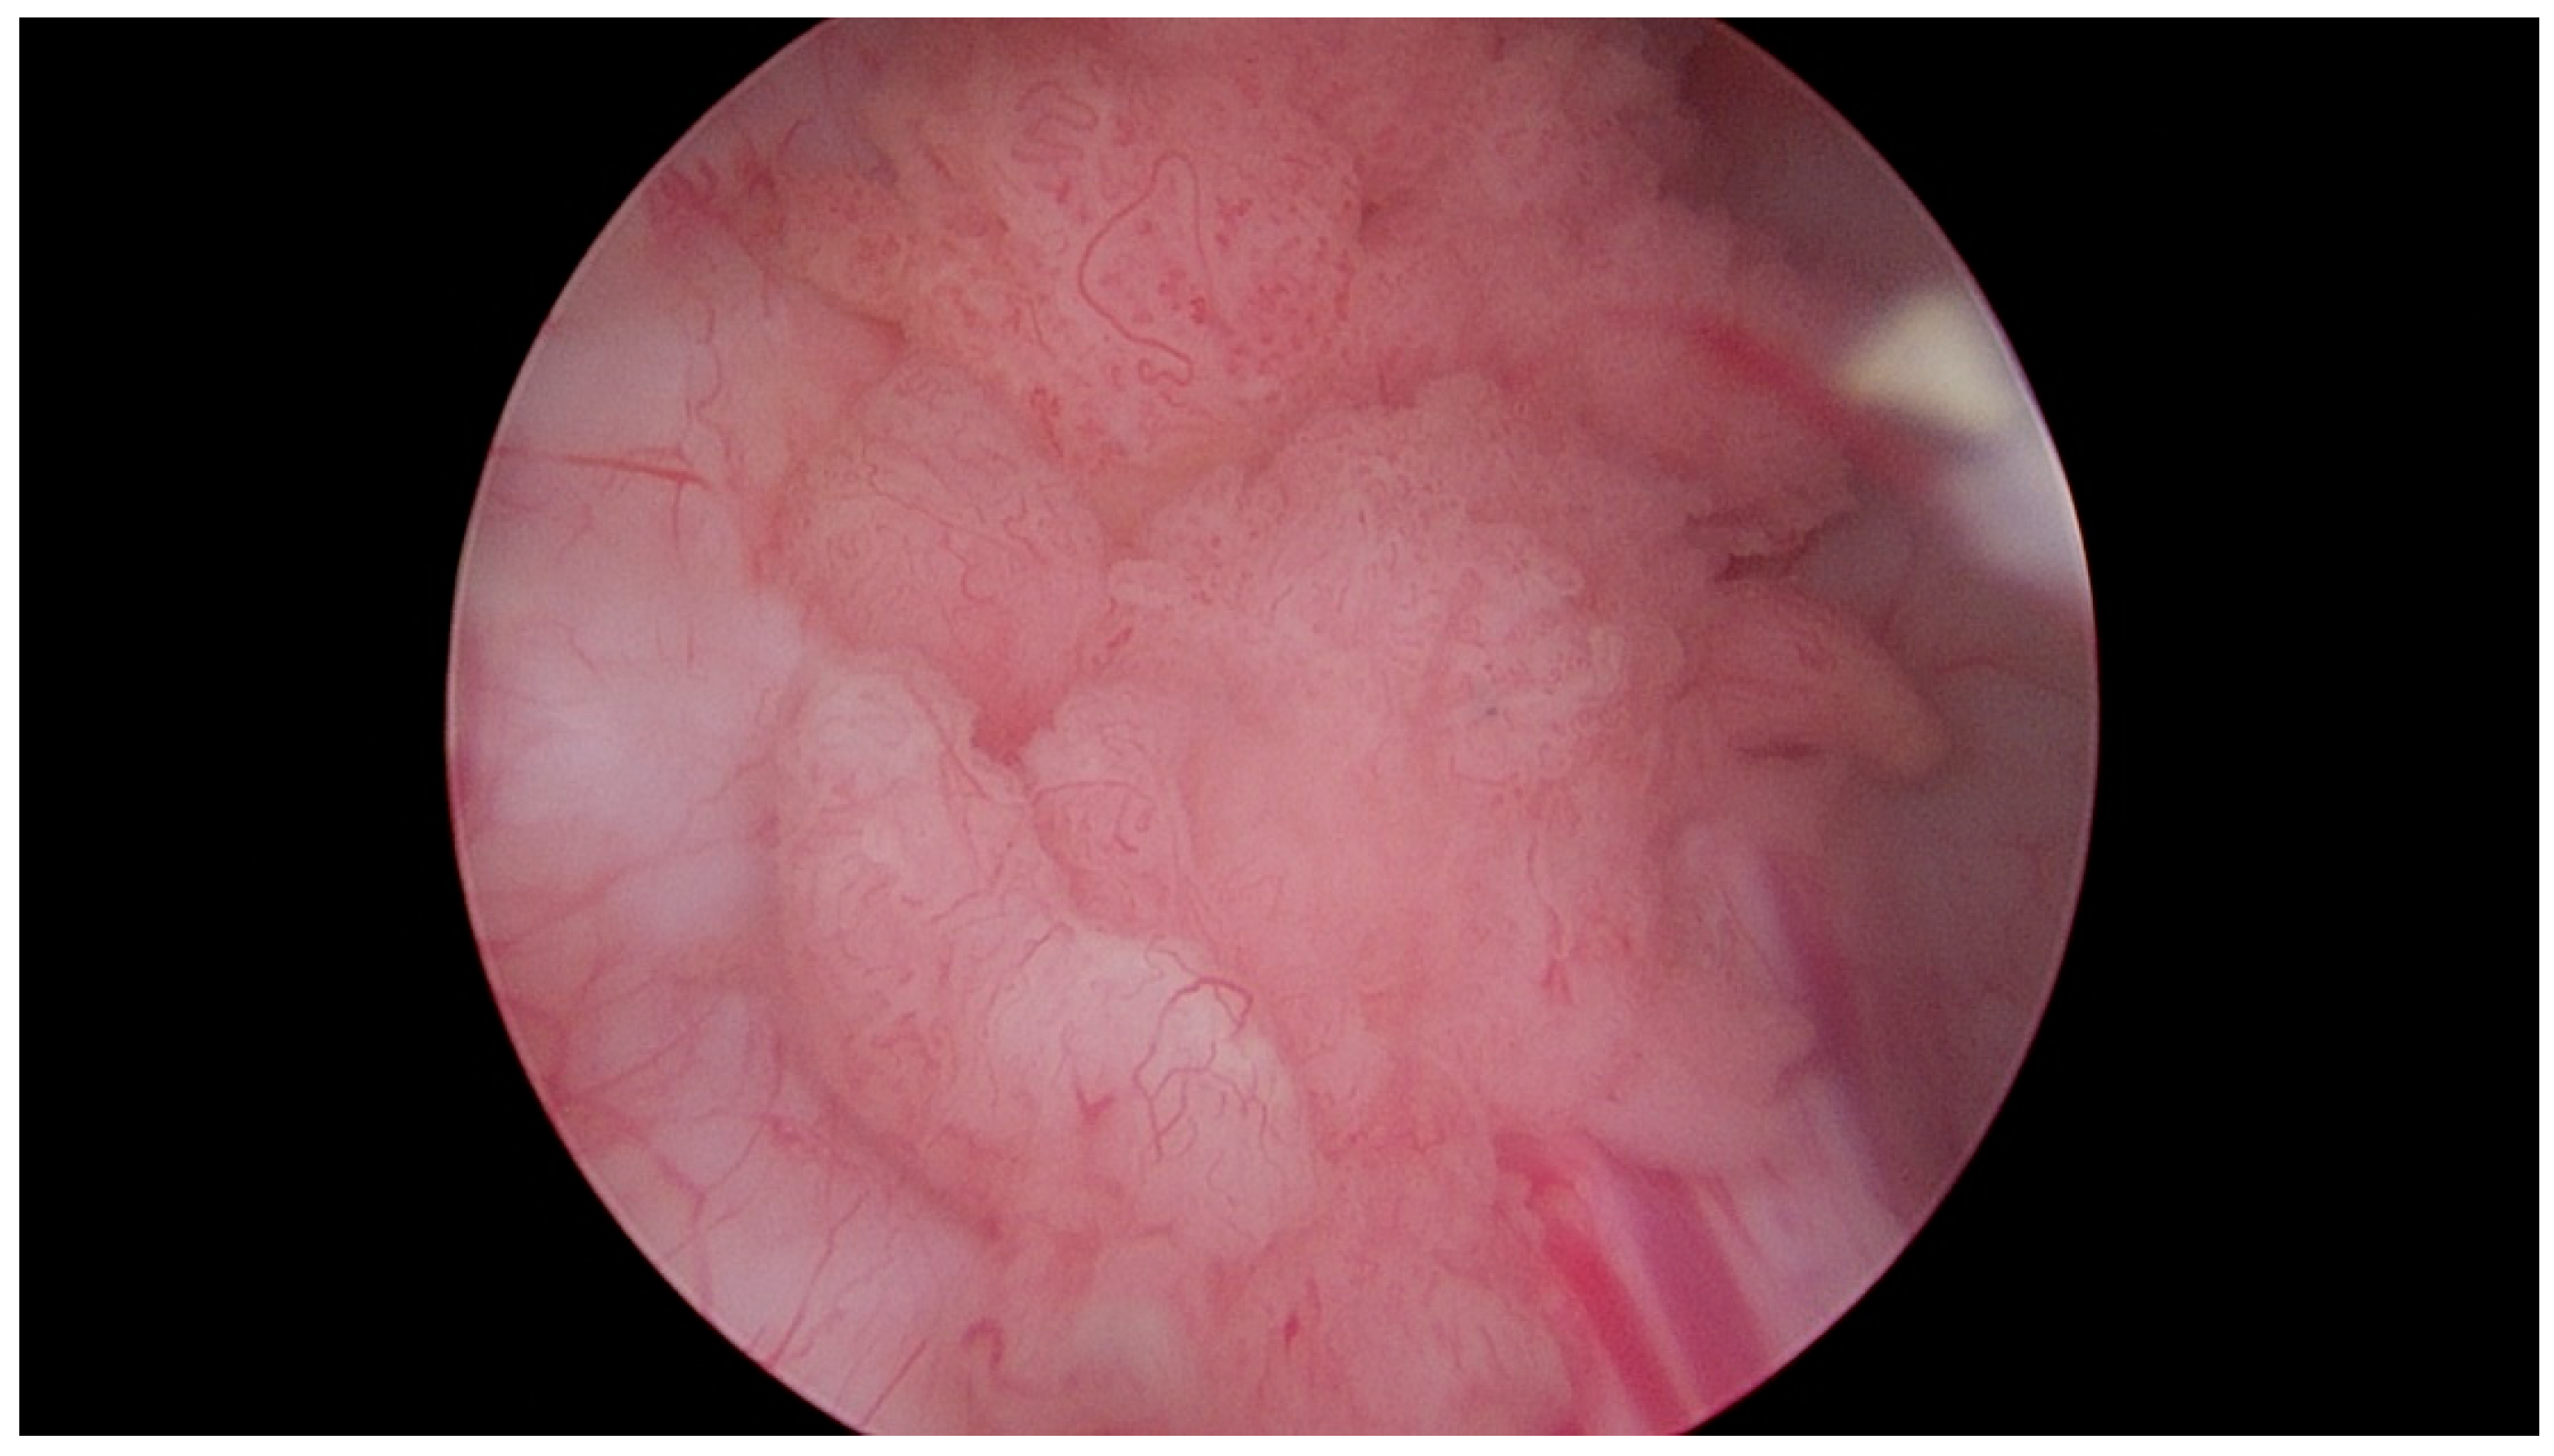

Figure 3.

Papillary urothelial carcinoma of the urinary bladder. Own study based on Ethical Approval of the University of Rzeszow, No. 29/05/2019. Titled 12. 2019, Evaluation of the efficacy of the in vitro photodynamic method in superficial bladder cancer, by M.D. Dominik Godlewski.